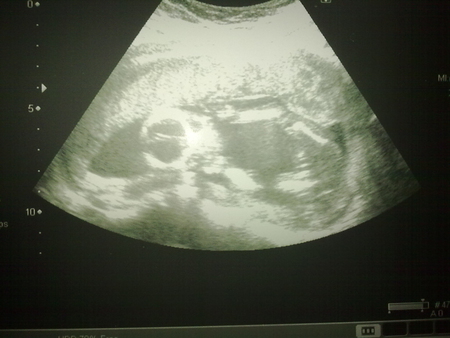

Блин я тоже вижу писечку на последней фотке.......Блин у вас точно мальчик!!!!

у меня еще 8го будет УЗИ,и потом еще 21числа,если три раза скажут мальчик,то придется поверить!